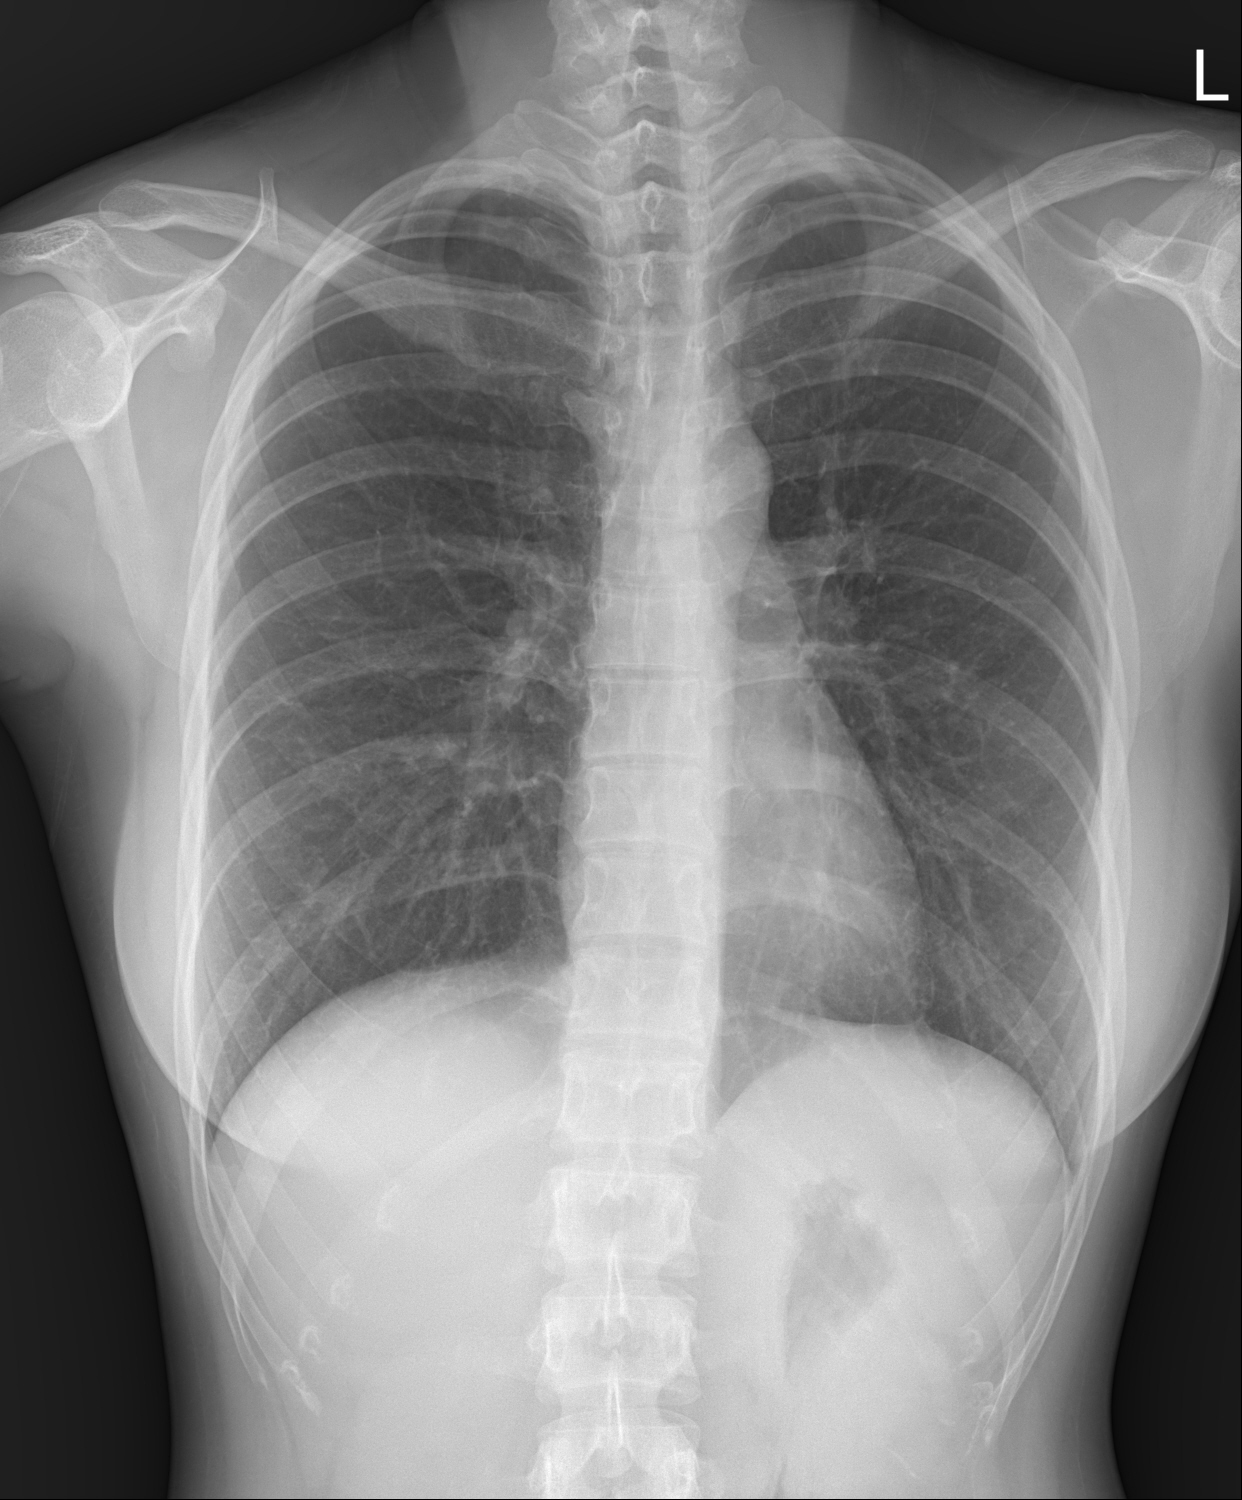

흉부 X-ray는 의료 현장에서 가장 널리 사용되는 영상검사 중 하나로, 폐와 심장, 흉곽 구조를 빠르게 확인할 수 있습니다. 방사선을 이용해 촬영하며, 폐렴·결핵·폐암과 같은 호흡기 질환은 물론, 심장 크기와 혈관 상태까지 평가가 가능합니다. 간단하면서도 비용이 저렴하고 검사 시간이 짧아 건강검진, 응급실, 외래진료 등 다양한 상황에서 활용됩니다.

- 폐렴 – 폐 조직에 염증이 생겨 흰색 음영이 나타납니다.

- 결핵 – 상엽 부위의 결절이나 석회화, 공동(cavity) 소견을 확인할 수 있습니다.

- 폐암 – 종괴, 결절, 또는 비정상적인 폐 음영을 통해 발견 가능하며, 조기 발견을 위해 CT 추가 검사가 권장됩니다.

- 기흉 – 폐가 수축되어 흉강 내 공기가 찬 모습을 확인할 수 있습니다.

- 심장비대 – 심장의 크기와 모양을 통해 심장질환 여부를 추정합니다.

- 늑막질환 – 흉수(pleural effusion)나 섬유화 소견을 확인합니다.